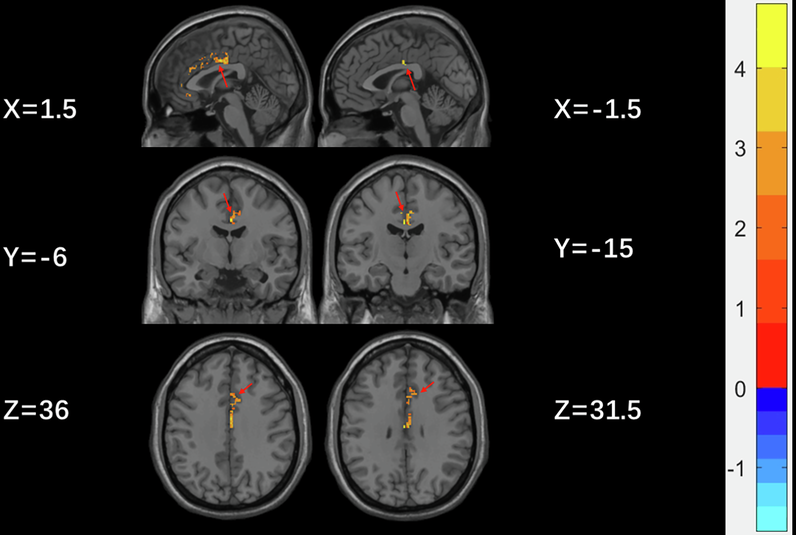

Fig. 1: Clusters with significant differences in GMV of the ACC between male and female MDD individuals with SI based on two-sample t-tests.

Red and blue colors denote increased and decreased GMV. The color bars indicate the T-value (1000 permutations with TFCE correction).